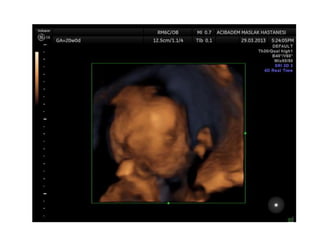

Binder Phenotype

a flat profile and depressed nasal bridge.

Short nose, short columella, flat naso-labial angle and

perialar flattening

Isolated Binder Phenotype transmission would be

autosomal dominant

Binder Phenotype can also be an important sign of

chondrodysplasia punctata (CDDP)